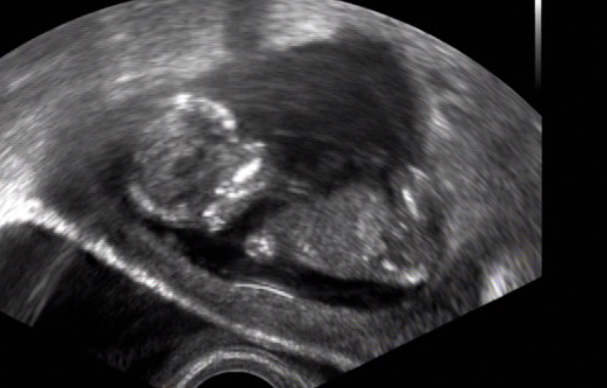

[883491]ja tam teda nevidim vubec nic,ani samotne mimi zda tam teda je vubec zabrane cele

[883496] nee to je jen kousííček právě s pindííkem nejspíše :D mám natočené video tak jsem to pauzla a udělala print screen :)